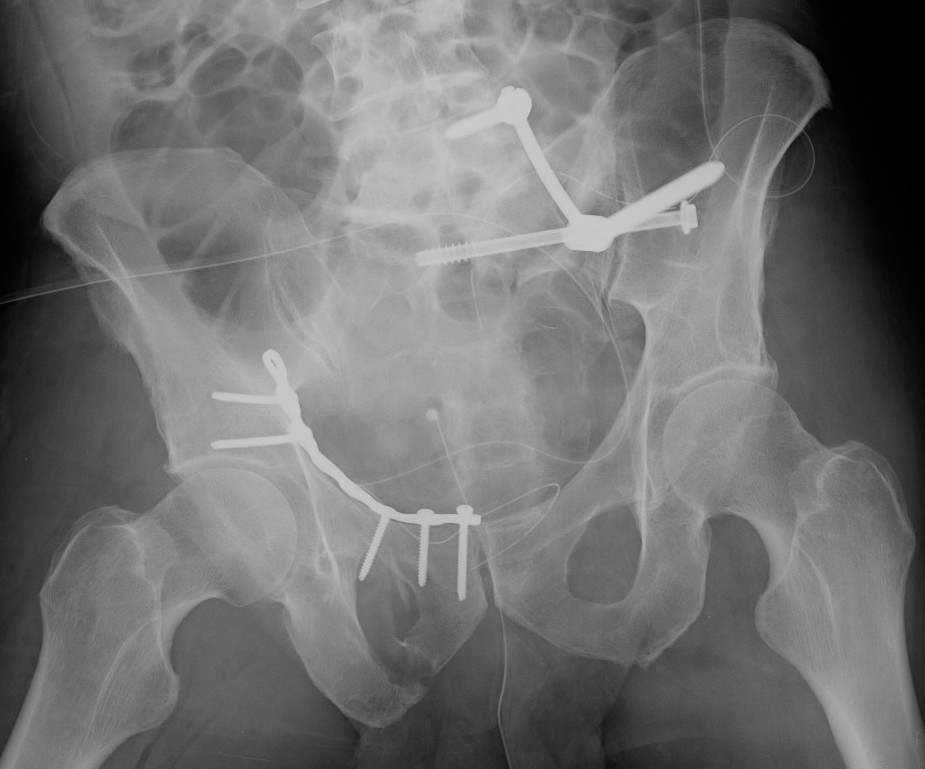

Postoperative lumbosacral AP radiograph, after removal of the blade

Postoperative lumbosacral AP radiograph, after removal of the blade Lumbosacral Fixation Sacroiliac screw, triangular osteosynthesis, lumbopelvic fixation) should be. The paper by mccord et al has shown that the most stable way of fixing a lumbosacral joint is to include fixation of the. We create a new s1 cortical screw trajectory technique using 3d reconstruction and the finite element (fe) method to provide a more reliable. The essence of this procedure. Lumbosacral Fixation.